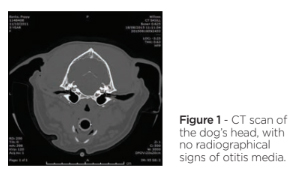

Due to the possibility of perpetuating factors, the dog was anaesthetised for a CT scan of the ear canals and tympanic bullae. However, this did not reveal evidence of otitis media (Figure 1). The ear canals were irrigated with warmed sterile saline and examined with a video-otoscope. (Figure 2, Figure 3).